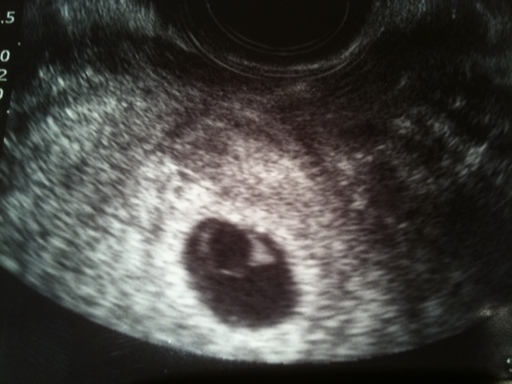

¾È³çÇϼ¼¿ä Àú´Â Áö±Ý ¿À´Ã·Î 7ÁÖ4Àϵưí ÁúÃÊÀ½ÆÄ·Î ¿À´Ã ºÃ´Âµ¥ ¾Æ±â°¡ ³Ê¹« ÀÛ´ä´Ï´Ù....

¾Æ±âÁýÀº 18mmÀÌ°í ¾Æ±â´Â °íÀÛ2.8mm¹Û¿¡ ¾ÈµÈ´Ù°íÇϳ׿ä..

¾Æ±â°¡ ³Ê¹« ÀÛ¾Æ ÇüÅ´ Àß º¸ÀÌÁö ¾Ê¾Ò°í ½ÉÀå¶Ù´Â °ÍÀº º¸¿´½À´Ï´Ù.±×¸®°í ³È²µµ ”œ½À´Ï´Ù

¼±»ý´Ô²²¼ ÀÏÁÖÀÏÈÄ¿¡ °Ë»çÇØ¼ ¾Æ±â°¡ Ä¿Á®ÀÖÁö ¾ÊÀ¸¸é À¯»êÀ¸·Î »ý°¢µÉ¼öµµ ÀÖ´Ù´Â À̾߱⸦

Çϼż ³Ê¹« ¿ì¿ïÇϳ׿ä...

2mmÁ¤µµ¸é 5ÁÖÁ¤µµÀ϶§ Å©±â¶ó³×¿ä...